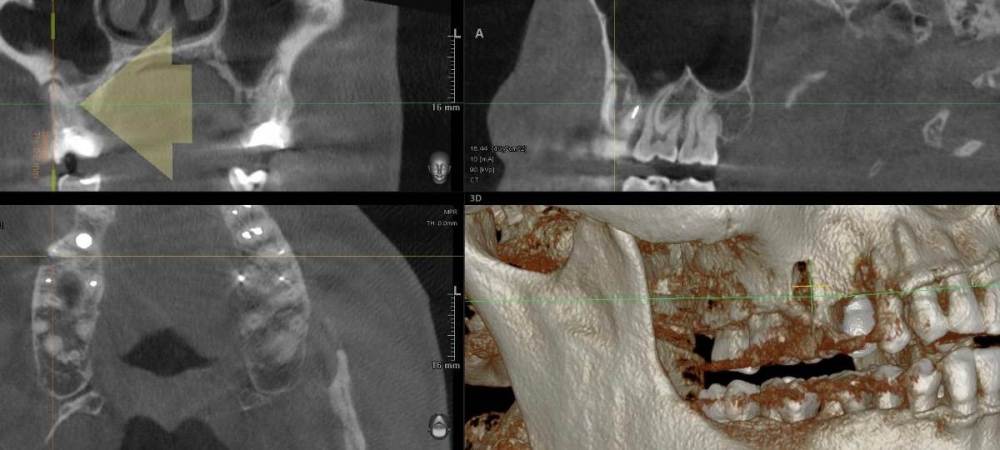

ict Опубликовано 21 июня, 2021 Поделиться Опубликовано 21 июня, 2021 первый снимок 2018г. второй свежий. Зуб был запломиброван больше 10 лет назад. За последние года киста увеличилась в размерах, вероятно пломба подтекала. Зуб не беспокоил. Что делать с кистой? Достаточно ли перепломбировать каналы? Ссылка на комментарий

ict Опубликовано 22 июня, 2021 Автор Поделиться Опубликовано 22 июня, 2021 (изменено) изначально пломбировалось вероятно резорцином, каналы вскрывались с трудом, легко прошло ультразвуком. Никак не беспокоило, редко незаметные ощущения типа почесывания при жевании. Пломба была с краю плоха, поэтому решил поменять. При вскрытии проблемного канала было подтекание крови, что насторожило врача, подумал что перфорировал корень. На неделю временно оставил под временной пломбой, зуб никак не беспокоил. Так как по рентгену не смог ничего увидеть (что канал нормально пройден), то запломбировал (второй снимок в первом посте) триоксидентом (первый снимок в первом посте), сверху жидкотекучий композит и оставил под временной пломбой. Промывал 0.5%, а не 3% раствором. Нашел еще снимок 2019 года, киста на 0.1 мм выросла за год по сравнению со снимком 2018г. (линию провел). Сейчас думаю оставить так и поставить постоянную пломбу или имеет смысл снова вскрыть и что-то делать. Прикрепил снимок от 2019 года Изменено 22 июня, 2021 пользователем ict Ссылка на комментарий